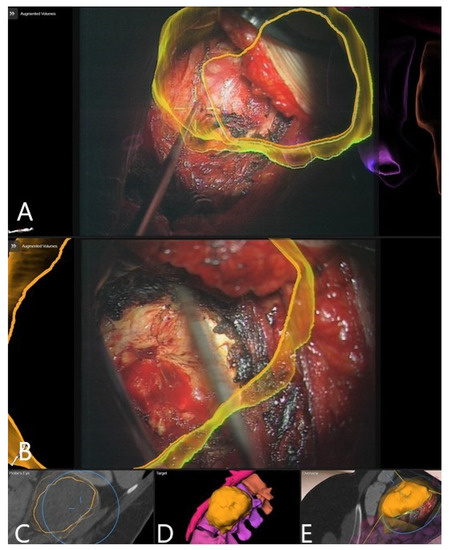

3.4. Augmented Reality

3.5. Clinical Application of iCT and AR